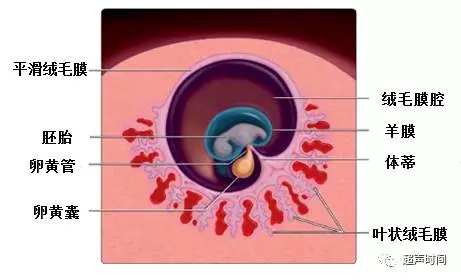

绒毛膜下血肿( Subchorionic hematoma,SCH)是指由于叶状绒毛膜出血,血液聚集在绒毛膜下与妊娠囊相间区域。借助图 1 和图 2这两张胚胎发育模式图,能帮助理解血肿的解剖位置。血肿总是在绒毛膜与子宫蛻膜之间,也就是不同大小的血肿总是在叶状绒毛膜、平滑绒毛膜与底蛻膜、包蛻膜之间。血肿与宫腔至少隔着包蛻膜,并不是在宫腔内。

图 2 胚胎发育第 7 周模式图